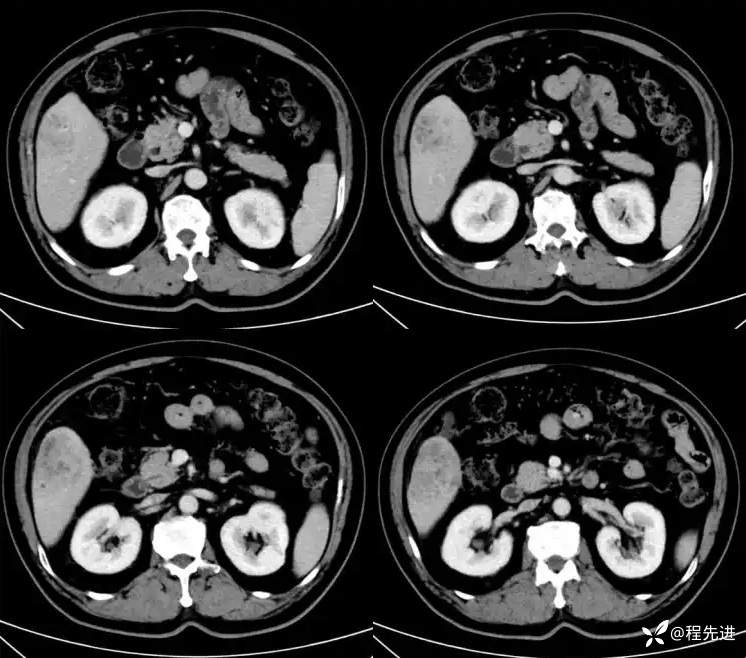

延迟期:

T1同反相位: